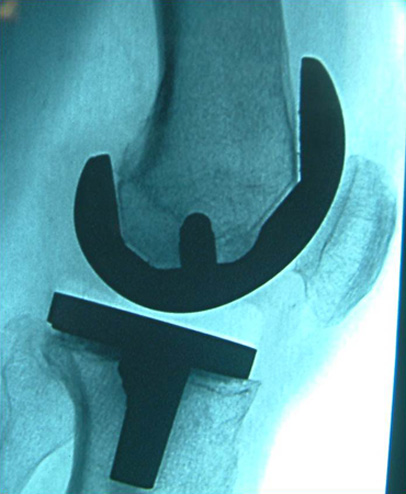

- Implantation von Totalendoprothesen an Hüft-, Knie und Schultergelenk inkl. Wechseloperationen